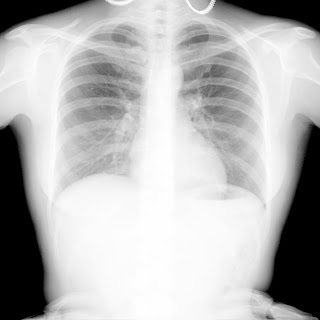

Флюорограма №18

Легені без вогнищево - інфільтративних змін. Корені не змінені. Синуси вільні. Серце норма.